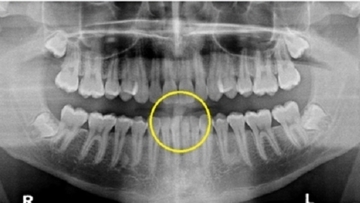

死亡の米大生「歯がズレた」原因は北朝鮮の拷問…裁判所が認定

北朝鮮に拘束され米国に帰国直後に死亡した米バージニア大学生、オットー・ワームビアさん(当時22歳)の両親が北朝鮮に賠償を求めていた訴訟で、米ワシントンDCの連邦地方裁判所は24日、北朝鮮に対し5億01...